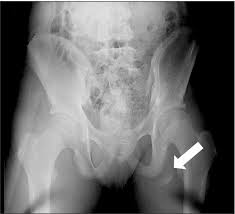

Apophyseal Avulsion Fracture Ric Size from i1.wp.com They are serious injuries that most often occur in people aged 65 and older. People who fracture their hip sometimes need surgery to fix the fracture or replace the hip. These injuries can be extremely painful, and may take months to heal. An avulsion fracture is a fracture in which part of the bone breaks off from the rest of the bone. Sometimes you can get an avulsion fracture in other bones, such as the hand. They are more common in children avulsion fractures are caused by trauma. What causes a hip fracture? Ebraheim's educational animated video describes the condition of avulsion fractures around the hip in adolescence.

Timely, accurate diagnosis is imperative so proper treatment can be initiated. Ebraheim's educational animated video describes the condition of avulsion fractures around the hip in adolescence. Call 999 and ask for an ambulance. I was doing high jump and twisted my body and in the process my muscle ripped my growth bone off. Hip fractures are classified according to their anatomical location as intracapsular, which involves the femoral head and neck, and extracapsular, which includes intertrochanteric, trochanteric, an. With an avulsion fracture, an injury to the bone occurs near where the bone attaches to a tendon or ligament. Symptoms of ankle avulsion fracture are similar to ankle sprain. Call your health care provider if your pain doesn't go away, or if you notice swelling. Preparing for an avulsion fracture in the ankle? Avulsion fractures of the hip and. Avulsion fracture of the iliac crest is an uncommon pathology. This happens when a muscle or tendon connected to the hip bone suddenly tightens so hard that it pulls off part of the bone. I am 15 and did it to my hip/ upper pelvic bone.

With an avulsion fracture, an injury to the bone occurs near where the bone attaches to a tendon or ligament. Anyone can suffer an avulsion fracture of the ankle, but athletes and children are more prone to them than the rest of us. This happens when a muscle or tendon connected to the hip bone suddenly tightens so hard that it pulls off part of the bone. Ebraheim's educational animated video describes the condition of avulsion fractures around the hip in adolescence. An avulsion fracture occurs when a small chunk of bone attached to a tendon or the hip, elbow and ankle are the most common locations for avulsion fractures in the young athlete. If you think you've fractured your hip, you'll need to go to hospital as soon as possible. In acute avulsion fractures, there is usually a clear preceding traumatic incident. When to seek medical help. The causes of hip fracture are very different in young and elderly patients. With age, the bones can become weak and brittle. Other causes include cancer and injury. They usually happen when a bone is moving one way, and a tendon or ligament is suddenly pulled the opposite way. Hip apophyseal injuries in young athletes are a fairly rare problem, and often go unrecognized by health professionals.

Acute Avulsion Of The Iliac Crest Apophysis In An Adolescent Indoor Soccer from www.jbsr.be I am 15 and did it to my hip/ upper pelvic bone. An avulsion fracture is a fracture in which part of the bone breaks off from the rest of the bone. When the fracture happens, the tendon or these fractures most often affect bones in the elbow, hip, and ankle. What causes a hip fracture? There are numerous sites at which these occur. Hip pain in children is always a potentially serious and needs urgent assessment. Teenagers are more likely to have this injury than younger children. Hip fractures can limit mobility and independence.

Pain in the hip area may be referred from the knee joint or from structures in the inguinal canal, testis (including torsion) and lower abdomen, or from the lower back. Teenagers are more likely to have this injury than younger children. The causes of hip fracture are very different in young and elderly patients. Other causes include cancer and injury. Hip fracture occurs in approximately 341,000 persons in the united states each year. Read about causes, treatment options, available mobility devices, tips for recovery, and more. This happens when a muscle or tendon connected to the hip bone suddenly tightens so hard that it pulls off part of the bone. In acute avulsion fractures, there is usually a clear preceding traumatic incident. A hip fracture is a break in the bones of your hip. A hip fracture is a common injury, especially in people with osteoporosis. I was doing high jump and twisted my body and in the process my muscle ripped my growth bone off. A broken hip in older people is often partly the result of weakening bones from osteoporosis. This most commonly occurs at the ischial tuberosity where the hamstrings attach, or the iliac pain at the bony part on the front of the hip may be an anterior superior iliac spine avulsion fracture.